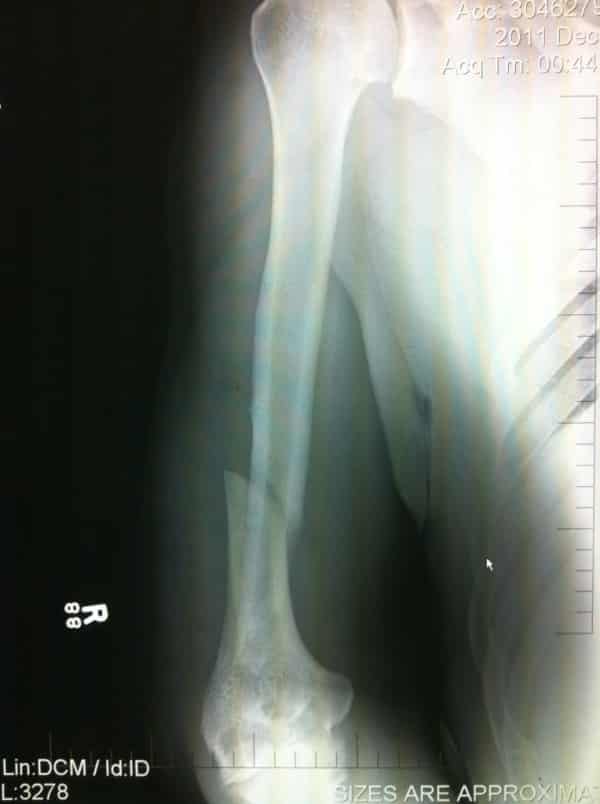

Vía Twitter, UFC ha publicado la imagen que vemos arriba en pantalla en donde se aprecia una Radiografía del brazo (codo) del peleador brasileño Antonio «Minotauro» Nogueira luego de sufrir una luxación tras una Kimura aplicada por Frank Mir ayer sábado 10 de diciembre de 2011 durante el evento UFC 140: Jones vs. Machida. Tambía

Rayos X del brazo de Antonio Nogueira tras ser roto por una Kimura por parte de Frank Mir en UFC 140 (10.12.11) / Twitter.com/UFC

Vía Twitter, UFC ha publicado la imagen que vemos arriba en pantalla en donde se aprecia una Radiografía del brazo (codo) del peleador brasileño Antonio «Minotauro» Nogueira luego de sufrir una luxación tras una Kimura aplicada por Frank Mir ayer sábado 10 de diciembre de 2011 durante el evento UFC 140: Jones vs. Machida.